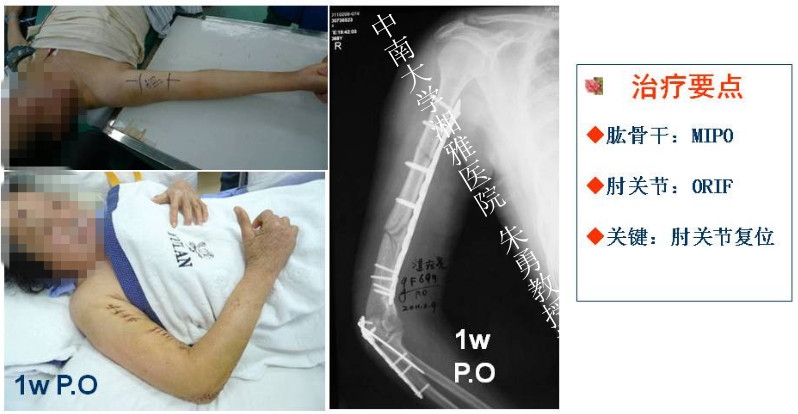

肘关节是人体内在稳定性最强的关节之一,骨性结构和软组织结构复杂。单纯肘关节脱位时没有骨折,但常伴有关节囊、韧带和其他软组织的损伤。复位后常比较稳定,很少出现关节不稳定和退变。相反,复杂的肘关节脱位是关节囊、韧带损伤的同时合并一处或多处骨折,治疗比较困难。为此,骨科在线创伤主编、北京大学人民医院付中国教授特邀请中南大学湘雅医院朱勇教授分享他治疗复杂肘关节脱位的心得,在此也希望广大骨科同仁踊跃投稿(典型病例和学术文章),来稿请发至:orth@orthonline.com.cn